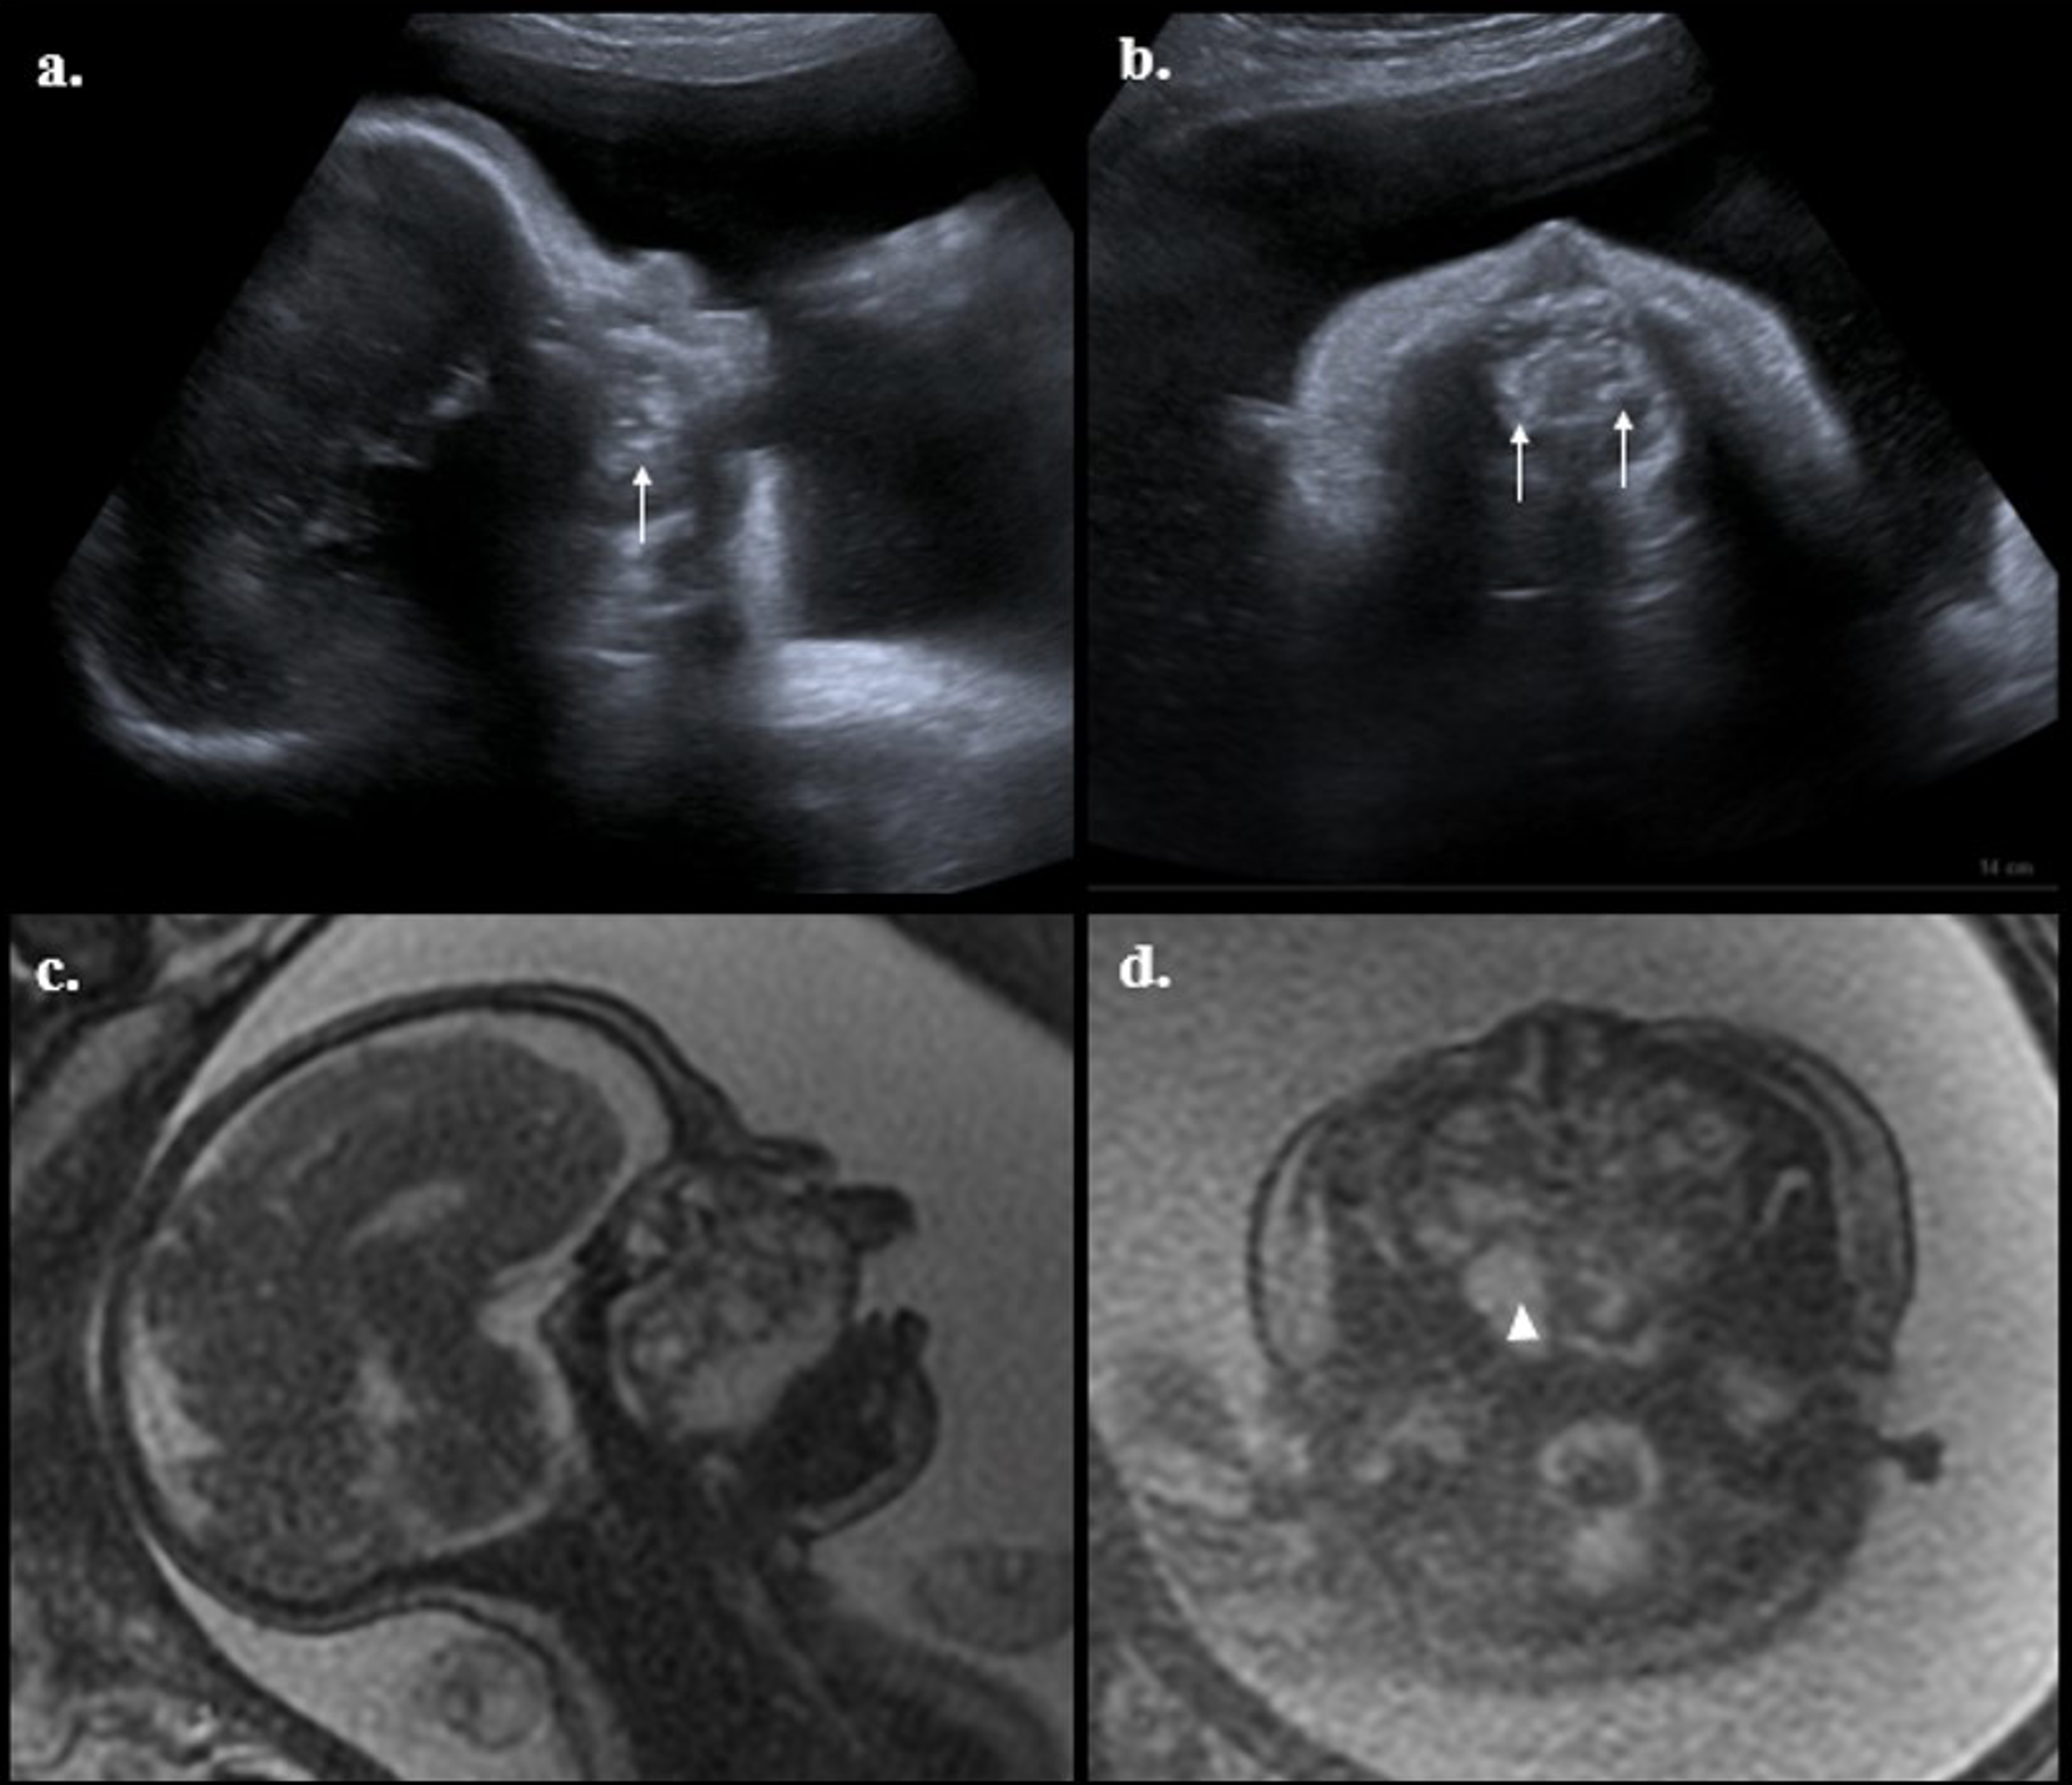

En las fotografías a y b, se muestra imagen ecográfica de corte sagital y axial con masa en paladar con ecogenicidad mixta, en su interior calcificaciones (flechas). Las fotos c y d muestran imágenes de resonancia secuencias ponderadas en T2, corte sagital y axial con masa heterogénea con bordes lobulados, expansiva, que ocupa la nasofaringe y orofaringe, de componente sólido y quístico por zonas hiperintensas (cabeza de flecha).

Figura 1 Ecografía obstétrica y resonancia fetal.

Por persistencia de actividad uterina asociada a dificultad respiratoria secundaria a distensión abdominal, se realizó amniodrenaje de 1.500 cc de líquido amniótico claro, sin complicaciones, y se obtuvo cariotipo fetal euploide 46, XX. Se completó el estudio de la anatomía fetal por resonancia magnética, secuencias ponderadas en T2 corte sagital y axial, documentando la existencia de una lesión con bordes lobulados, expansiva, que ocupaba la nasofaringe y orofaringe, de componente predominantemente sólido por la presencia de zonas hiperintensas, con un tamaño de 37 x 47 mm, sin estigmas de compromiso de las órbitas o de sistema nervioso central (Figura 1). Durante la evolución la paciente presentó ruptura espontánea de membranas, por lo que se indicó terminación de la gestación por cesárea bajo protocolo de EXIT (7). Se obtuvo recién nacido de sexo femenino, de 2.180 g, Apgar 5, 8 y 9. Durante la adaptación neonatal y bajo intubación orotraqueal la recién nacida presentó bradicardia (60 latidos min) y ausencia de esfuerzo respiratorio, por lo que requirió reanimación neonatal con adrenalina y solución salina por vía umbilical acompañada de masaje cardiaco, con retorno de la circulación espontánea.